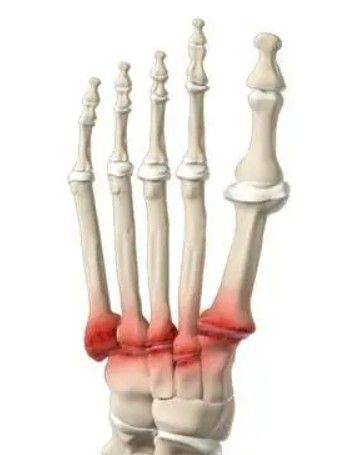

A artrose é uma doença que causa o desgaste da cartilagem, aquele tecido que reveste as extremidades dos ossos nas articulações, permitindo que eles deslizem suavemente. Na Artrose Tarso Metatarsal, essa cartilagem se deteriora justamente nas articulações que acabamos de descrever.

Com o tempo, a cartilagem pode desaparecer por completo, fazendo com que os ossos se atritem diretamente. Esse atrito gera:

- Dor

- Inflamação

- Rigidez

- A formação de esporões ósseos (chamados osteófitos, ou "bicos de papagaio").

É um processo degenerativo que avança gradualmente, afetando a capacidade do seu pé de funcionar corretamente. Pode ocorrer em uma ou em várias das cinco articulações tarso metatarsais.